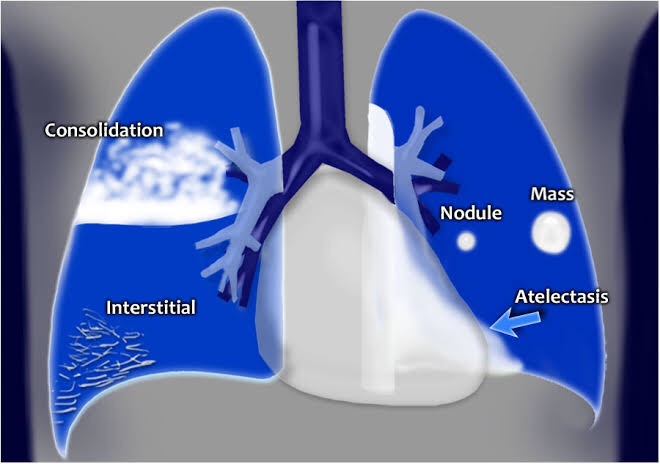

▪️Radiological forms:

- Fibrosis/Cavity – Post primary infection (Refer page 3)

- Consolidation – Primary infection (parenchymal): Refer page 5

- Collapse (Refer page 4)

- Tuberculous Pleural Effusion (Refer page 2)

- Miliary Tuberculosis –